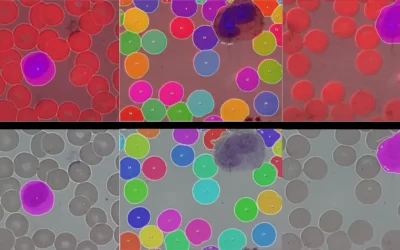

Automatic Detection and Classification of Leukocytes by Combining Microscopy Techniques with an Artificial Intelligence Algorithm

In cooperation with the company KML Vision, scientists at the Medical University of Vienna apply fluorescence techniques and machine learning to raise blood smear microscopy to a new level. They intend to apply AI algorithms to classify White Blood Cells into their...